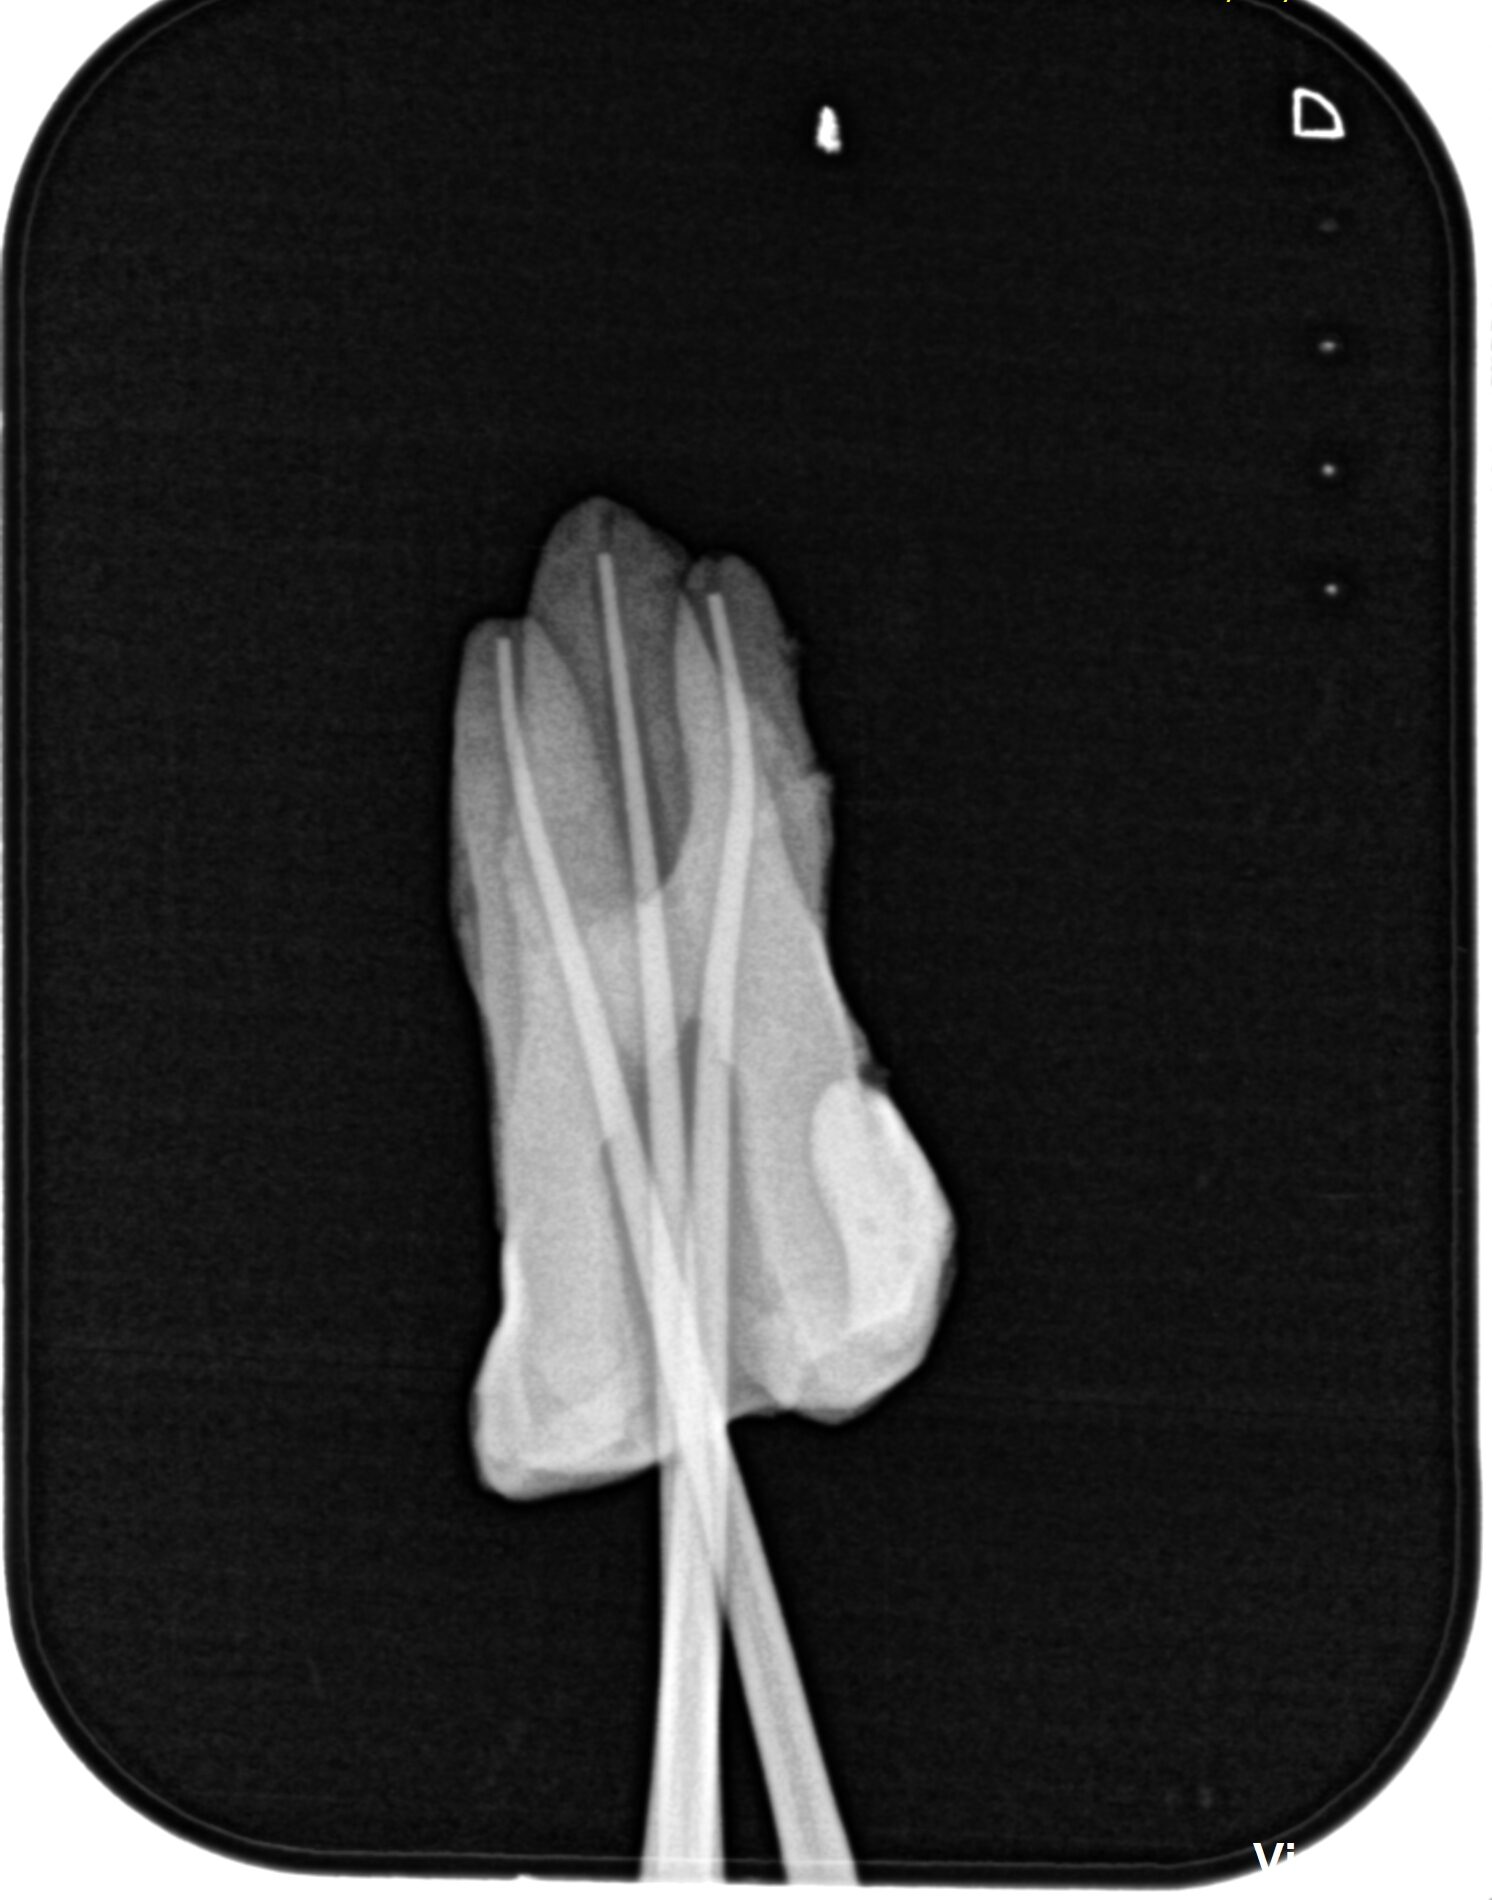

これが終われば作業長測定である。

次に根管形成の実際を説明した。

どう動かすか、サイズを下げるべきなのか?